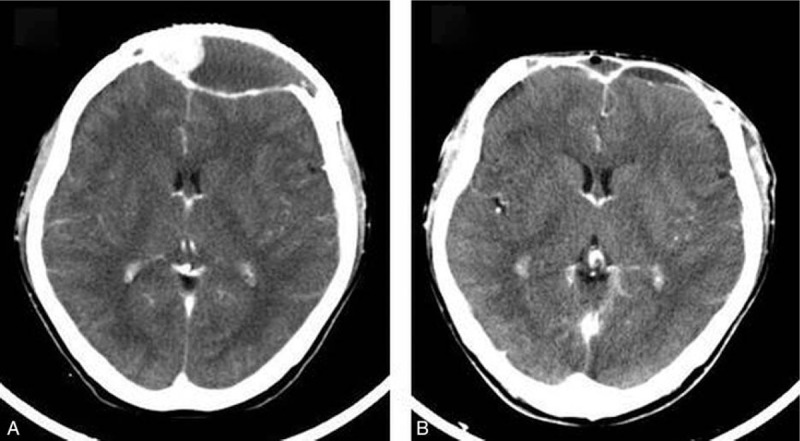

图示头颅增强CT示钛网下肿瘤复发(A);术后增强CT扫描显示肿瘤全切除,但也显示手术硬脑膜和头皮增强,提示残留肿瘤(B)

图源:参考文献[1]